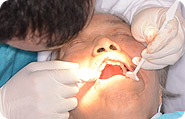

4微创安全

6TCI全程无痛